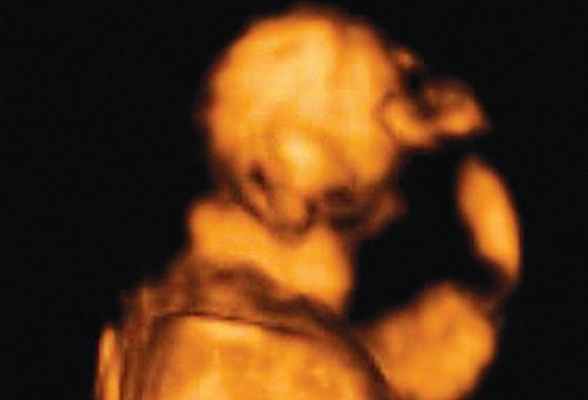

Использование трехмерного ультразвука, включая визуализацию поверхности, многоплоскостное и многослойное изображение, позволяет точно оценить различные черепно-лицевые структуры и их аномалии, включая расщелину неба (рис. 15, 16) и краниосиностоз. Изображения могут быть полезны для консультирования (рис. 17, 18). Использование 3D (рис. 19) может помочь дифференцировать закрытые и открытые швы. Использование 4D может быть использовано для оценки выражений лица.

Рисунок 15: Плод второго триместра с двусторонней расщелиной губы и неба. 3D аксиальный вид показывает потерю целостности (стрелки) губы (L) и неба (P) с обеих сторон.

Рисунок 17: Плод второго триместра с односторонней расщелиной губы.

3D поверхностное изображение лица плода показывает расщелину (стрелка) на верхней губе (L).